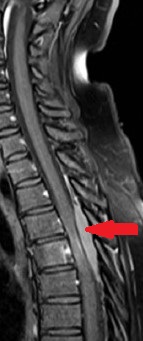

MRI σπονδυλικής στήλης που δείχνει εξωσκληρίδια συμπίεση στο επίπεδο Θ8 (Ευγενική παραχώρηση Dr. V. Penopoulos).